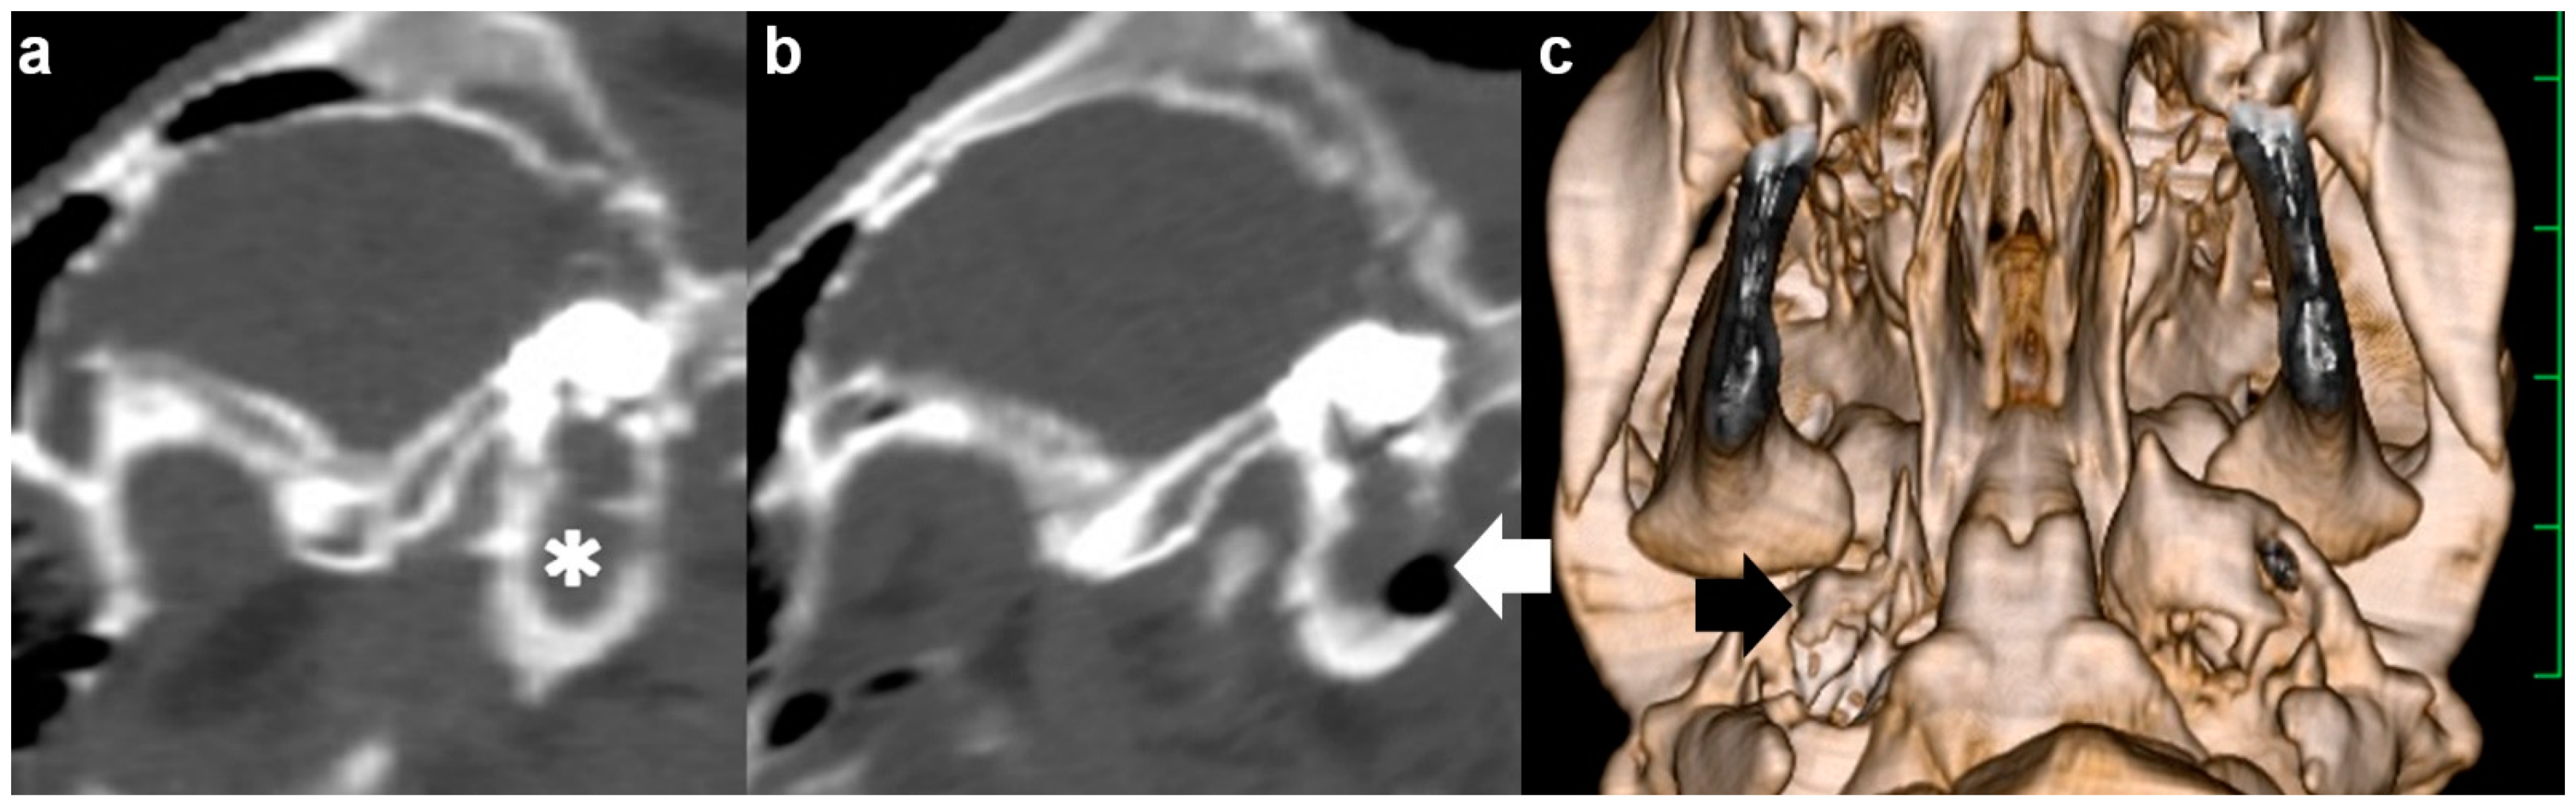

On admission, CT confirmed an accumulation of hyperattenuating contents into the entire cavity of the right tympanic bulla. On the transverse section, the wall structures were entirely hypoattenuating, and thick and rounded in shape due to being extended medially and ventrally (Figure 1a). On the sagittal section demonstrating the right tympanic bulla, the hyperattenuating contents were included in the oblong tympanic cavity due to being extended cranially and ventrally (Figure 2a). No abnormality was evident in the left tympanic bulla. The height, width, and length of the right tympanic bulla were 33.0, 27.2, and 29.2 mm, respectively, and tended to be large compared with those in the opposite left tympanic bulla (24.8, 25.7, and 24.2 mm, respectively) and the measurements (mean ± standard deviation) from five Holstein calves (25.9 ± 4.0, 25.9 ± 2.2, and 24.0 ± 3.3 mm, respectively) (Table 1). Compared with the maximum thickness of the ventral walls in the ears of five Holstein calves (1.9 ± 0.4 mm), the values increased severely in the right affected tympanic bulla (10.9 mm), and slightly in the left tympanic bulla (3.4 mm). Based on quantitative evaluation, the extension in the ventral wall contributed to the larger height of the right tympanic bulla.

A 1-month-old male Japanese Black calf with a body weight of 35 kg suddenly presented a head tilt toward the right, right ear droop, and bilateral horizontal nystagmus. Severe depression was also evident, together with declined physical performance. The calf’s difficulty in standing was suspected to be associated with vestibular ataxia. On admission, because of the quick development of the clinical signs, the severity of the neurological findings was scored 7 [9]. On the preoperative CT, the hyperattenuating contents were seen in the entire right tympanic bulla, in which the wall structures were not thickened and extended (Figure 1b). No difference between the left and right tympanic bulla was found in the height (17.4 mm vs. 15.7 mm), the width (28.5 mm vs. 27.2 mm), the length (26.1 mm vs. 23.0 mm), or the thickness (1.6 mm vs. 2.4 mm), respectively (Table 1). These four values were almost similar to the measurements from the five Japanese Black calves (in order, 21.0 ± 2.0, 26.2 ± 2.6, 22.6 ± 2.4, and 1.9 ± 0.3 mm, respectively).

A 2-month-old male Japanese Black calf with a body weight of 45 kg had developed a head tilt toward the left and left ear droop roughly 10 days previously. Neither depression nor abnormal physical performance were evident. A therapeutic response could not be obtained from a single injection of tilmicosin phosphate solution (10 mg/kg, SC; Micotil300, Elanco Japan, Tokyo, Japan) followed by the administration of an oxytetracycline hydrochloride solution (5 mg/kg, IM, q24, 7 days). On admission, the severity of the neurological findings was scored 2 [9]. The preoperative CT revealed that the left tympanic bulla was slightly extended ventrally and included the entirety of the hyperattenuating contents into the cavity, despite the right tympanic bulla not being abnormal (Figure 1c). No difference between the left and right tympanic bulla was found in the width (25.8 mm vs. 27.7 mm, respectively) or the length (23.7 mm vs. 22.4 mm, respectively), although the height of the right tympanic bulla (21.2 mm) was slightly extended compared with that of the left tympanic bulla (18.4 mm) (Table 1). The thickness in the ventral wall of the left tympanic bulla (5.1 mm) was larger than the measurements from the five Japanese Black calves.

Figure 1. Transverse computed tomography of the skull examined preoperatively ((a) Case 1; (b) Case 2; and (c) Case 3). The hyperattenuating materials (asterisk) are seen within the tympanic cavity. The scale is 25 mm.